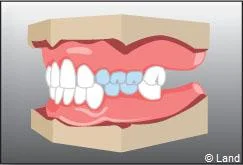

Lorsque des dents de lait ont été extraites trop tôt parce qu’elles étaient cariées, les dents de part et d’autre peuvent migrer et combler l’espace, bloquant ainsi l’éruption des dents définitives. Il est alors nécessaire de maintenir cet espace avec un appareillage spécifique appelé « mainteneur d’espace » jusqu’à l’évolution des dents définitives.